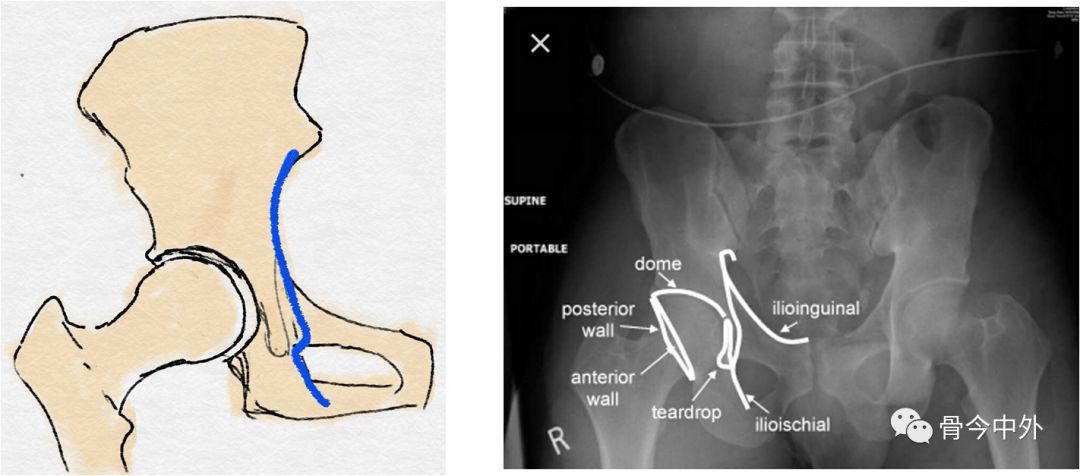

髂坐线:

连接髂骨内缘与坐骨内缘的弧线

反映髋臼内壁、四边体的完整性

泪滴:

U型的弧线

代表了髋臼的内缘